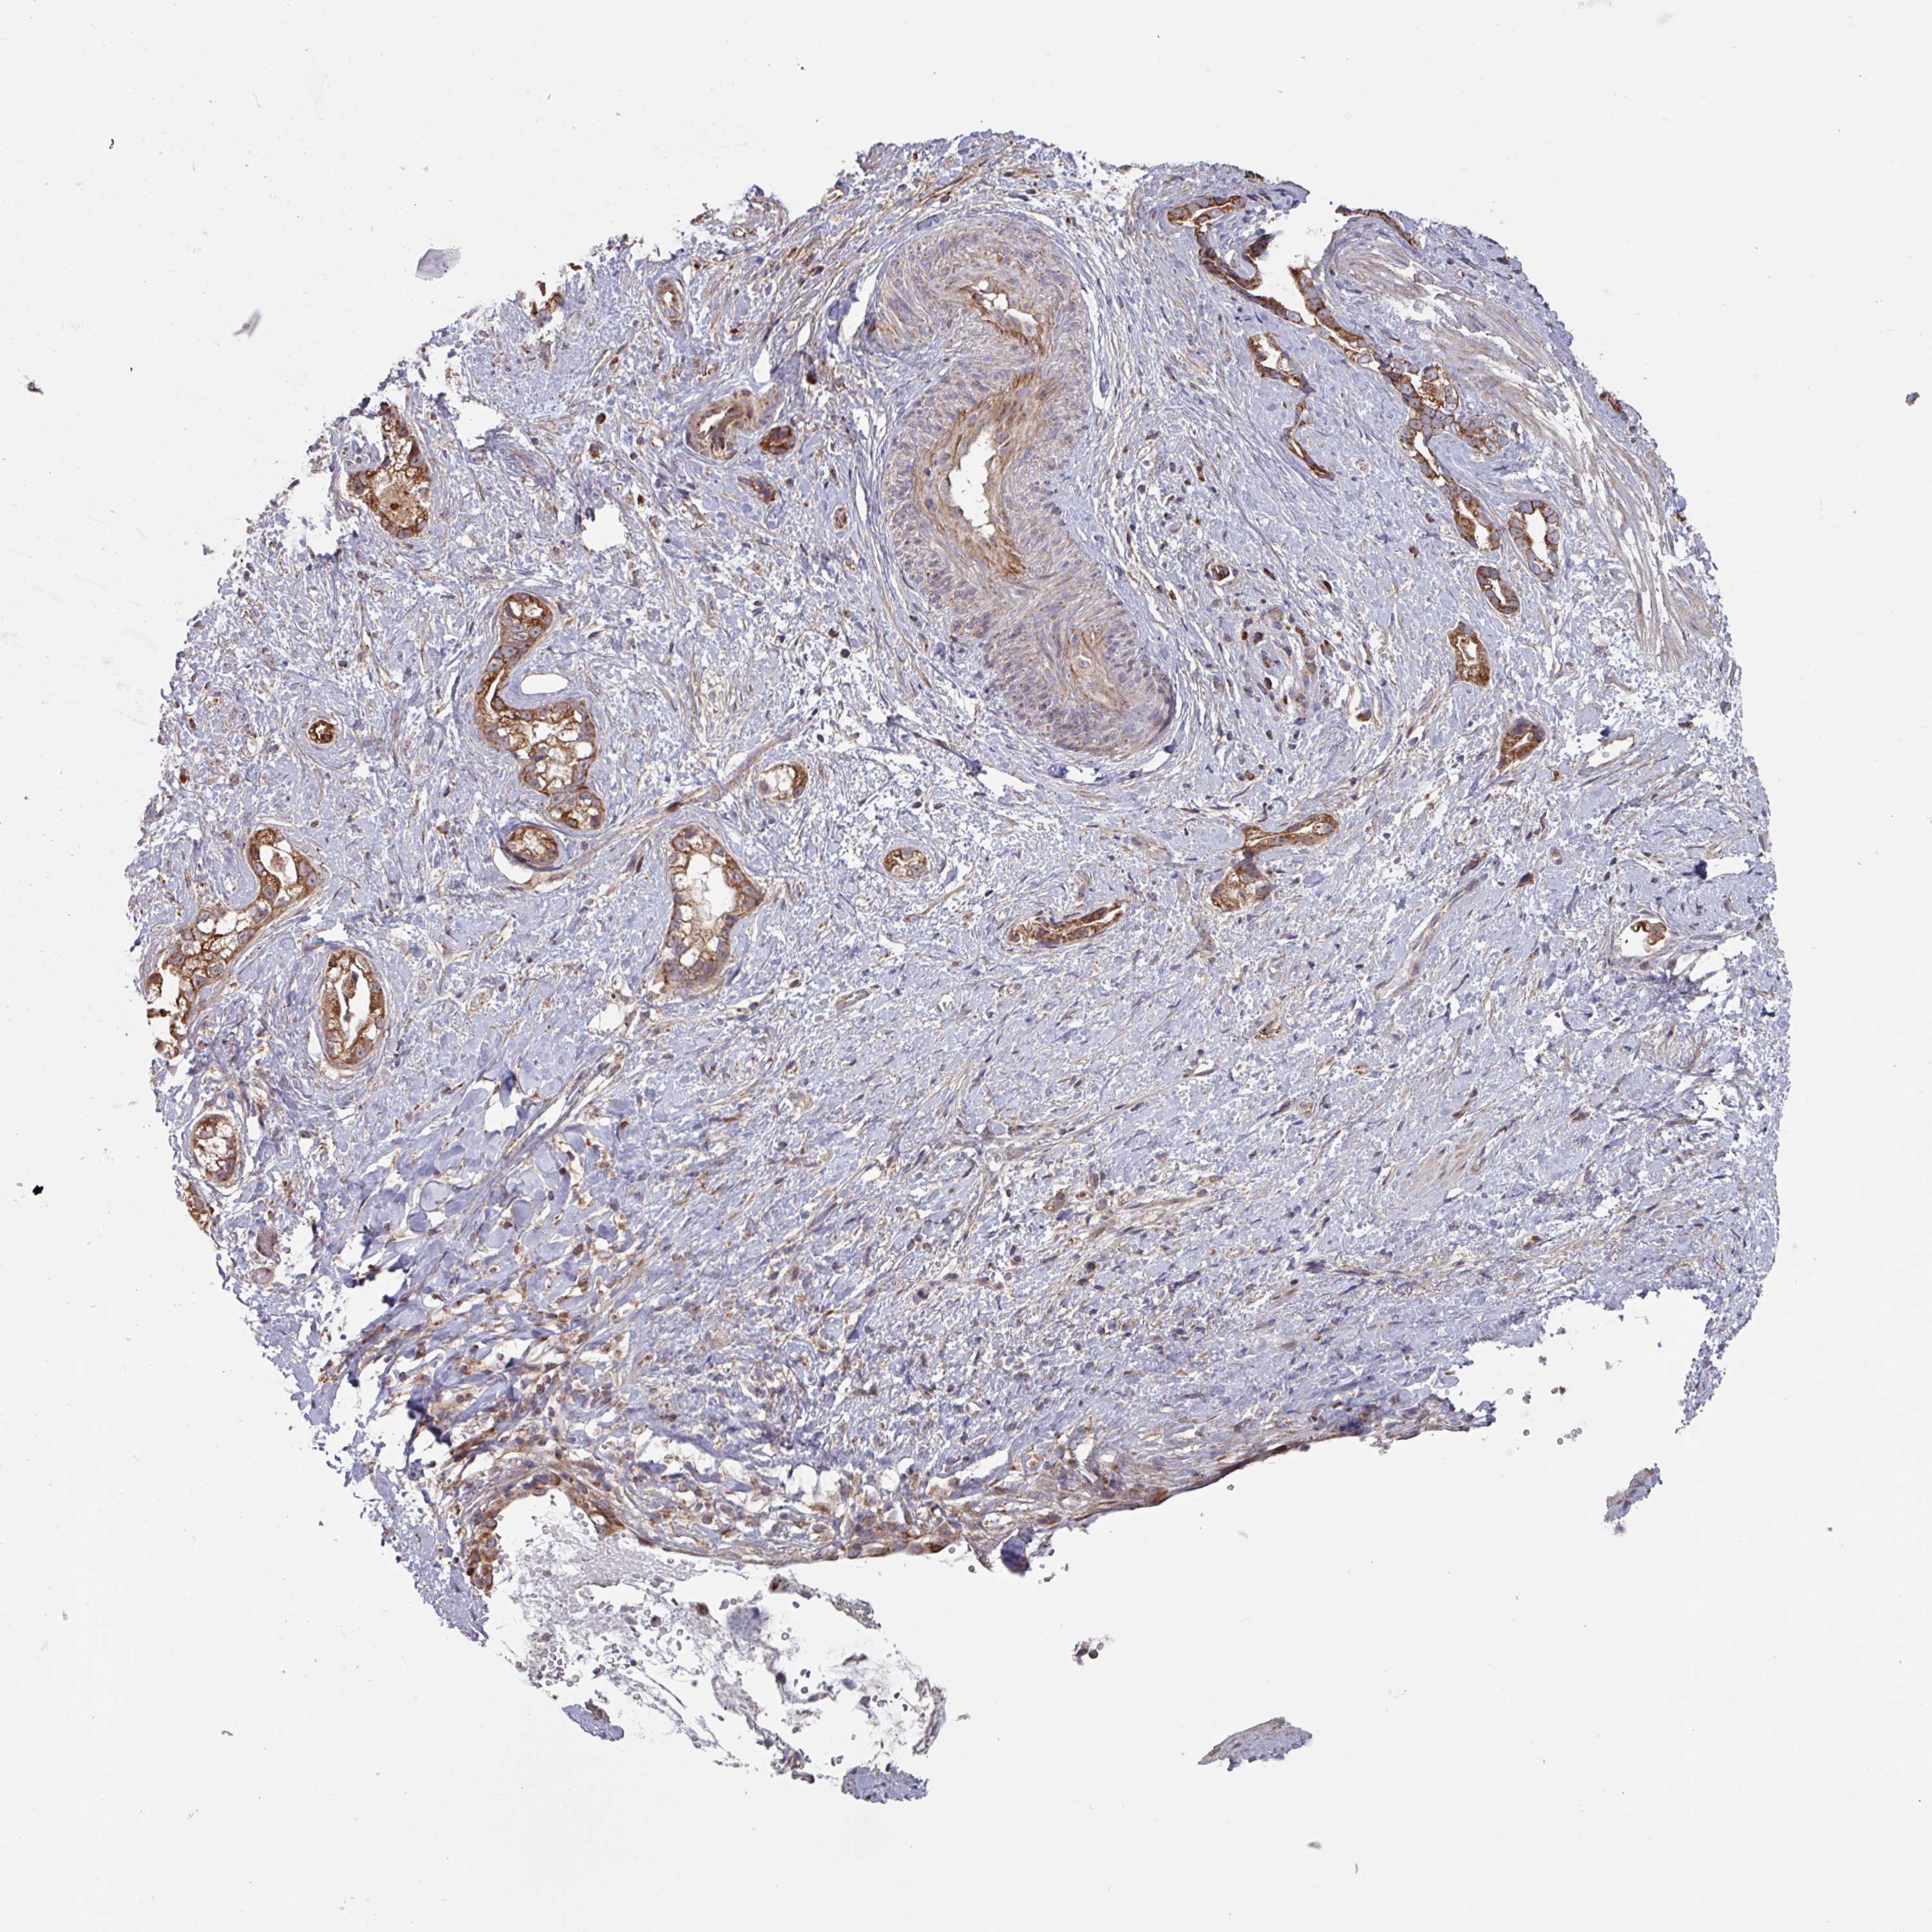

STOMACH CANCER - Protein expressioni

A mouse-over function shows sample information and annotation data. Click on an image to view it in a full screen mode. Samples can be filtered based on level of antibody staining by selecting one or several of the following categories: high, medium, low and not detected. The assay and annotation is described here.

Note that samples used for immunohistochemistry by the Human Protein Atlas do not correspond to samples in the TCGA dataset.

Antibody stainingi

Antibody staining in the annotated cell types in the current human tissue is reported as not detected, low, medium, or high, based on conventional immunohistochemistry profiling in selected tissues. This score is based on the combination of the staining intensity and fraction of stained cells.

Each image is clickable and will lead to virtual microscopy that enables deeper exploration of all samples and also displays staining intensity scores, fraction scores and subcellular localization as well as patient and tissue information for each sample.

Antibody HPA046647

Staining

High

Medium

Low

Not detected

Intensity

Strong

Moderate

Weak

Negative

Quantity

>75%

75%-25%

<25%

None

Location

Nuclear

Cytoplasmic/membranous

Cytoplasmic/membranous,nuclear

Adenocarcinoma, NOS